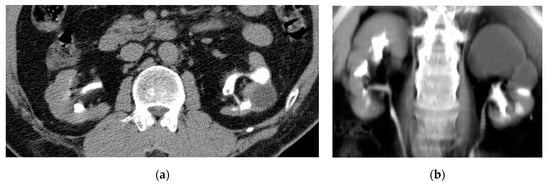

2.6. Emphysematous Urinary Tract Infection

| Emphysematous UTIs | Gas in the renal parenchyma, collecting system, bladder lumen and sometimes in the perirenal and perivesical tissue. |